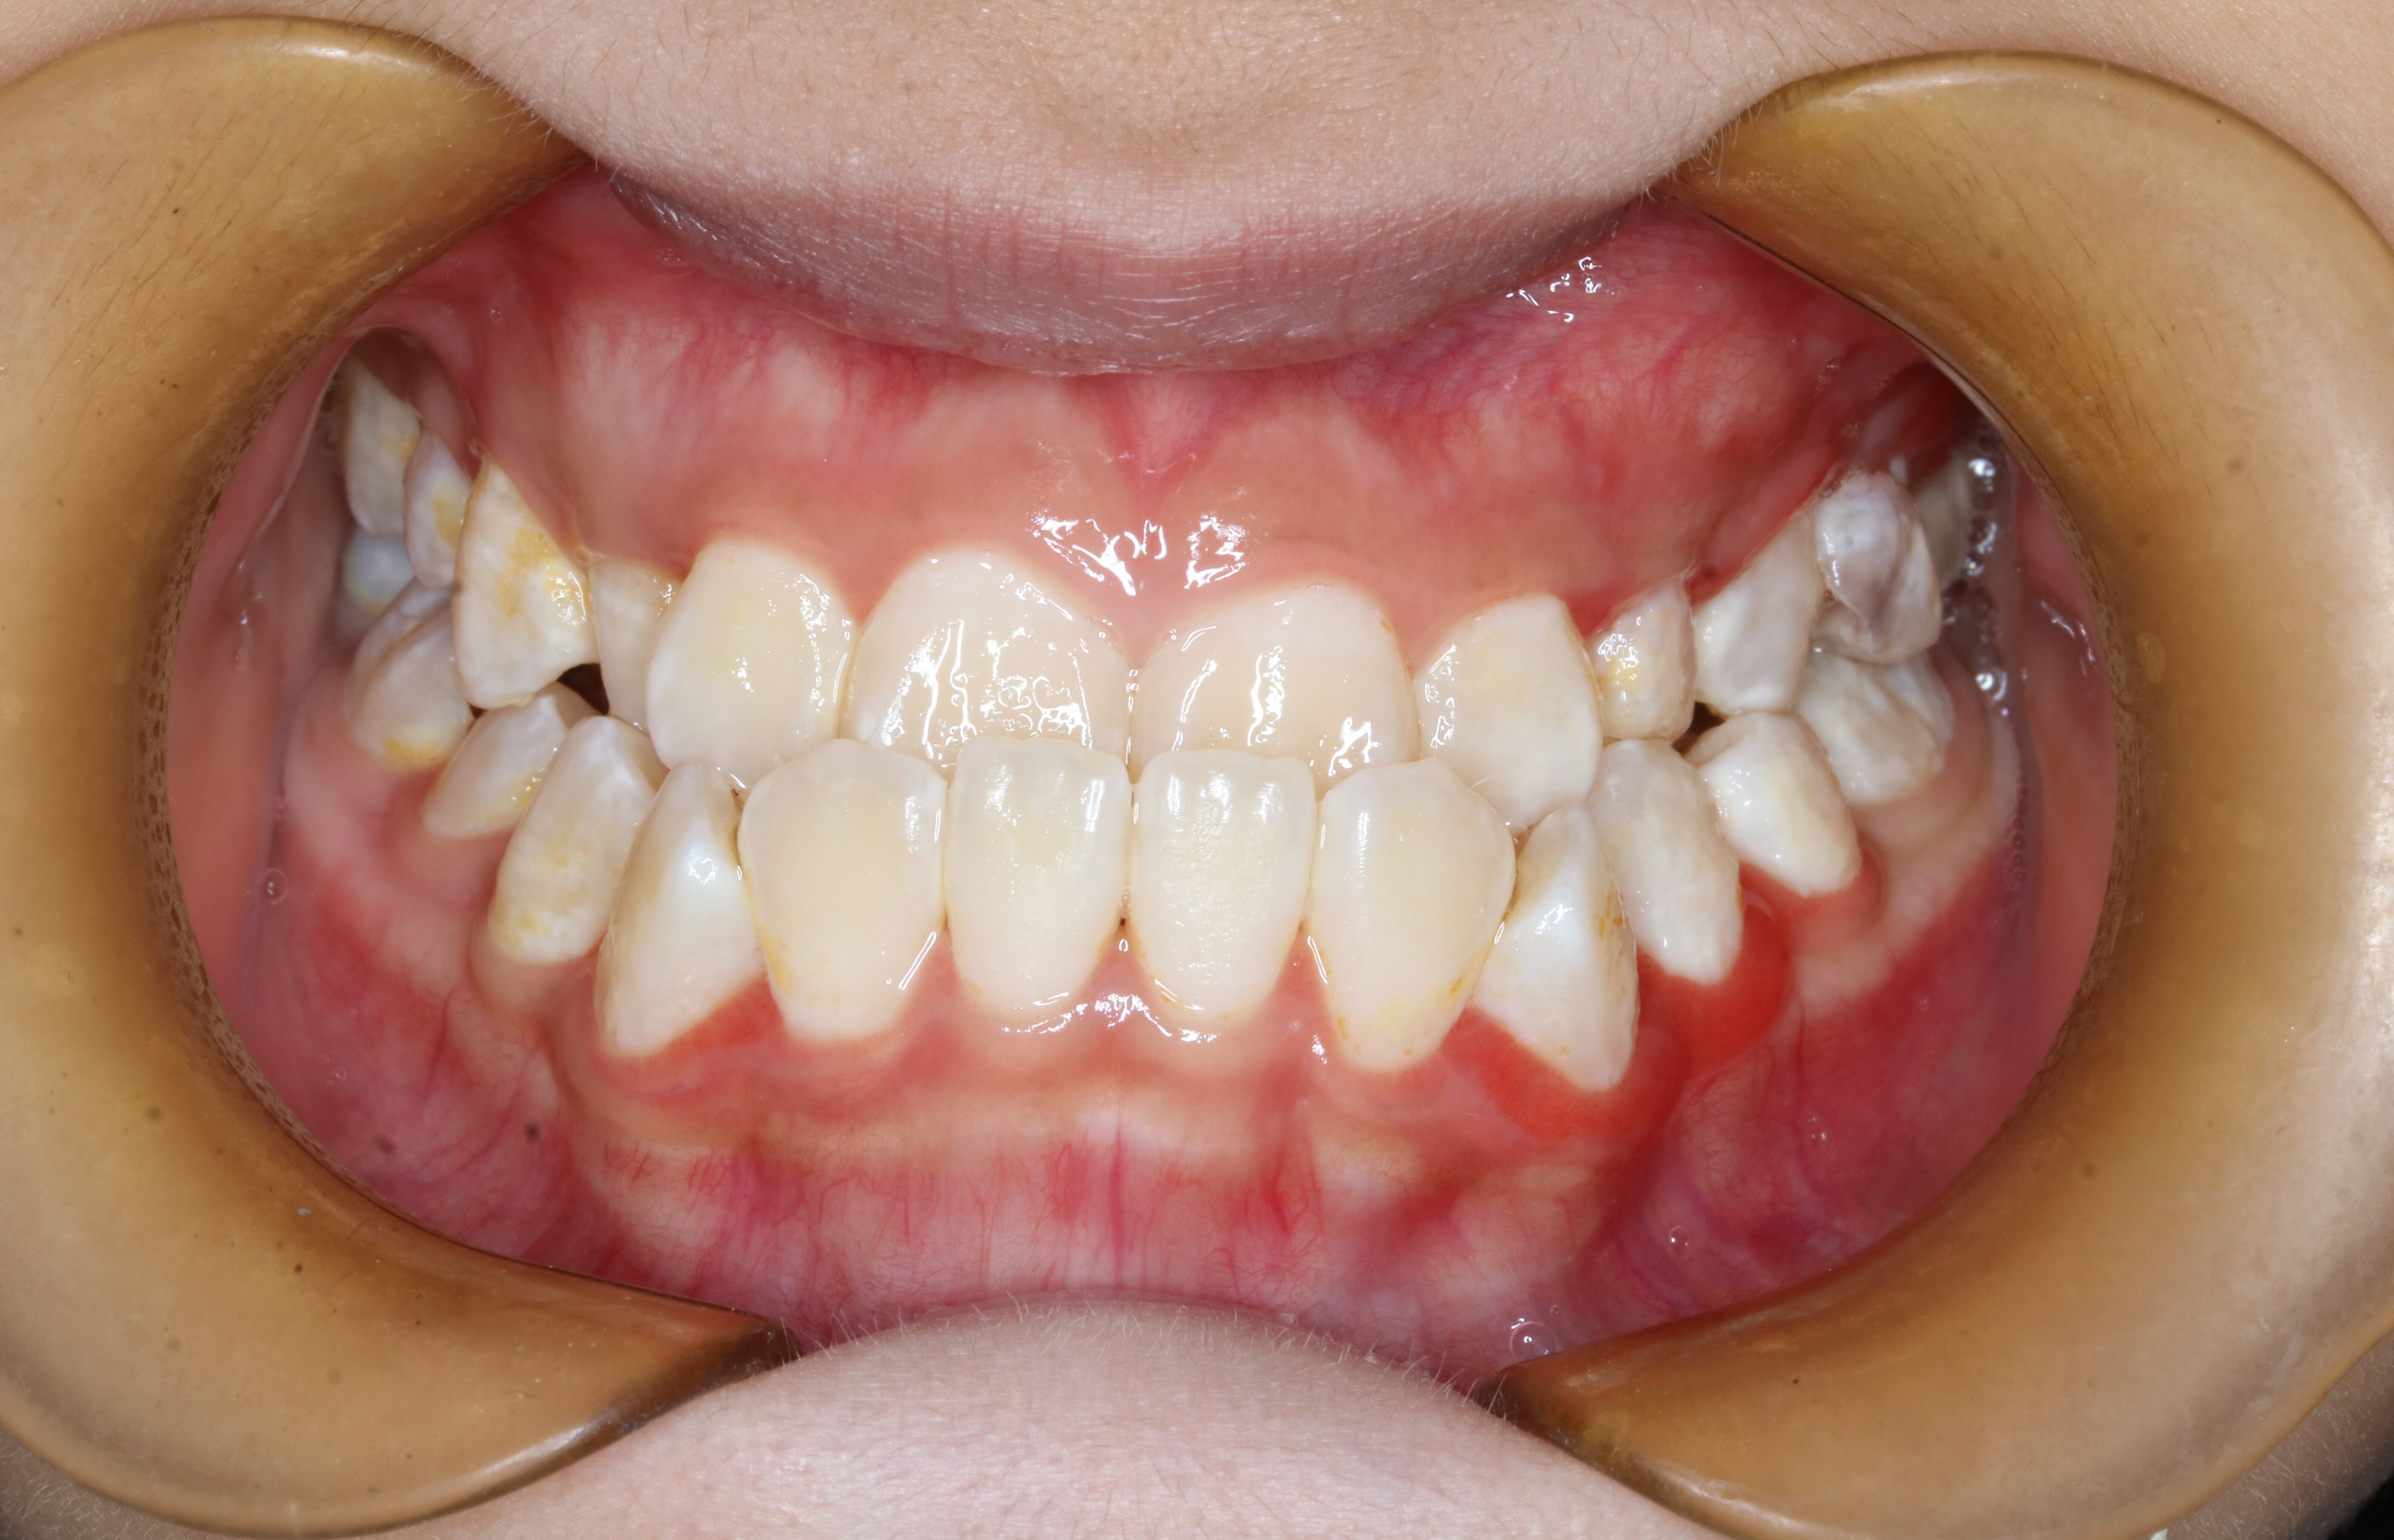

关于儿童牙齿矫正那些事(图3)

开颌

关于儿童牙齿矫正那些事(图4)

牙齿稀疏